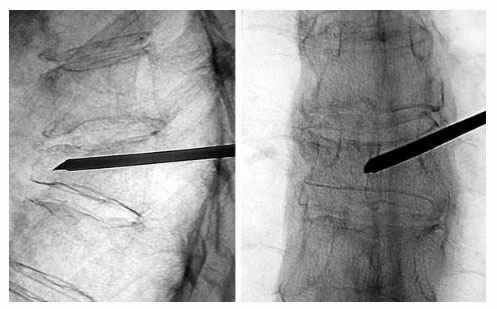

In vertebroplasty procedure, Pain Physicians inject a cement mixture into the fractured bone through a hollow needle in operation theatre under X-ray guidance under local anesthesia. Once cement gets hardened, the patient is free to leave the hospital and can go home on the same day. If the patient needs further observation after the procedure, a short stay in the hospital may be recommended.